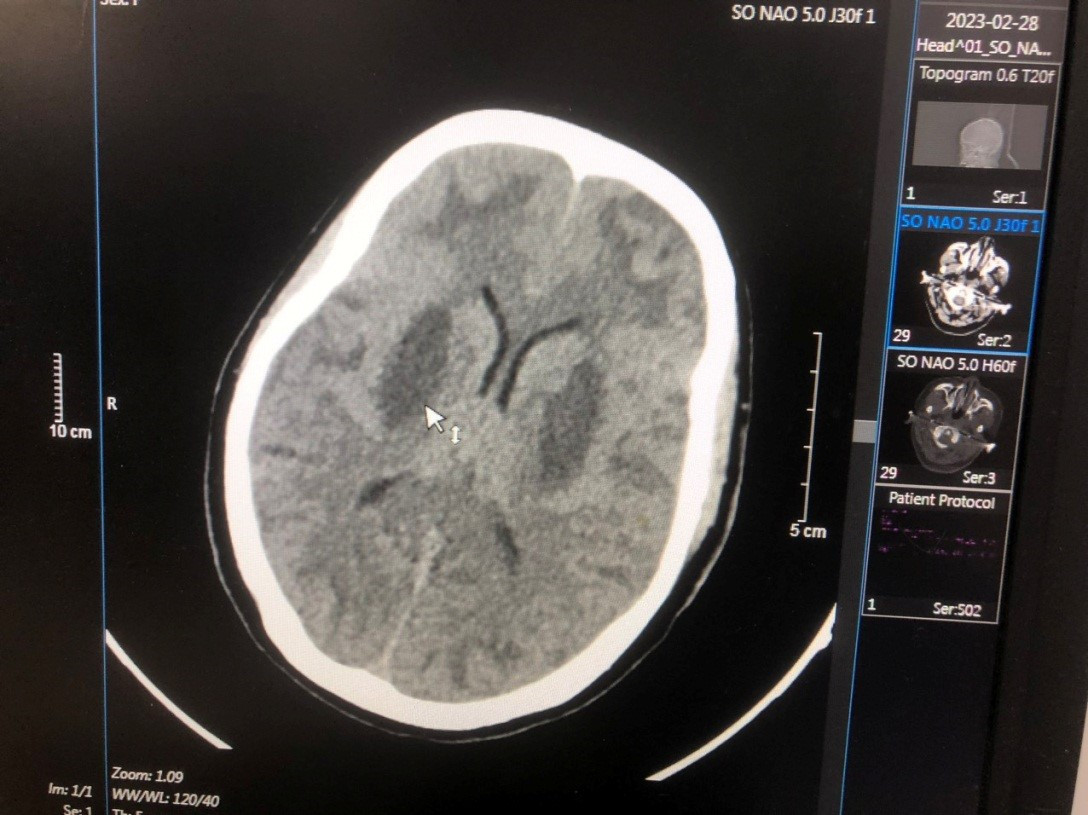

Vụ 37 công nhân bị ngộ độc methanol: Một người tổn thương não nghiêm trọng

Ngoài một trường hợp đã tử vong, 3 người ngộ độc nặng được điều trị tại Bệnh viện Bạch Mai trong tình trạng mắt, thần kinh bị tổn thương.

Vụ ngộ độc rượu có người tử vong: Nữ sinh nguy kịch bị di chứng não

Nữ nạn nhân nặng nhất trong vụ ngộ độc rượu chứa Methanol trước đó tại TP.HCM hiện đã xuất viện. Tuy nhiên, cô gái bị di chứng tổn thương não.